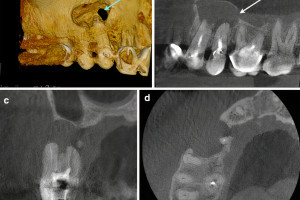

Радиационно-индуцированный некроз или остеорадионекроз характеризуется наличием обнаженной кости после проведения лучевой терапии. Открытая кость может полностью секвестрировать, что часто приводит к обнажению большего количества кости. Хотя кость, расположенная в любом месте челюсти, восприимчива к излучению, задняя часть нижней челюсти поражается чаще, чем другие области, потому что она часто находится в поле излучения, особенно когда в лечение включены лимфатические узлы. Может возникать интенсивная боль при периодическом отеке и дренировании вне полости рта. Однако многие пациенты не чувствуют боли при обнажении костей. Утрата нормальной структуры может нарушить целостность кости, а в некоторых случаях кость может сломаться.